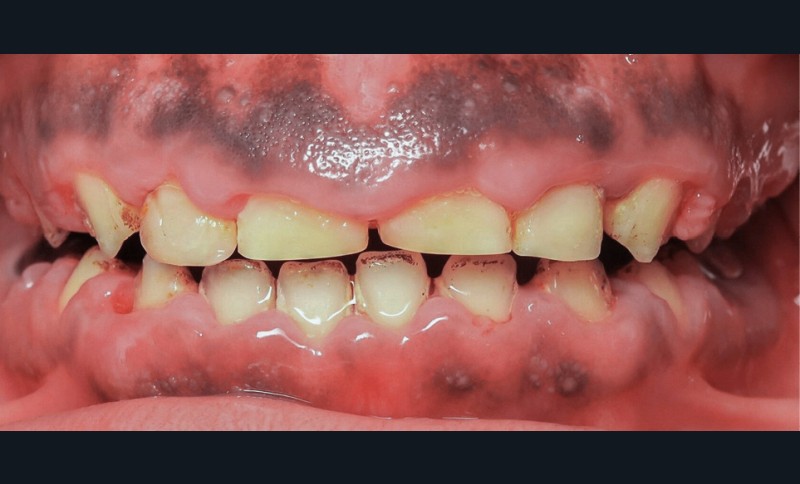

L’examen exobuccal met en évidence un profil dolichofacial et des anomalies majeures de structure dentaire (fig. 1). L’examen intrabuccal (fig. 2) montre :

- une hypoplasie sévère de l’émail ;

- une hyperplasie gingivale inflammatoire ;

- des hauteurs coronaires très réduites ;

- des couronnes pédodontiques sur les premières molaires permanentes ;

- des caries sur 17 et 27 ;

- des défauts d’éruption des quatre deuxièmes molaires permanentes ;

- de nombreux diastèmes et l’absence des dents de sagesse.